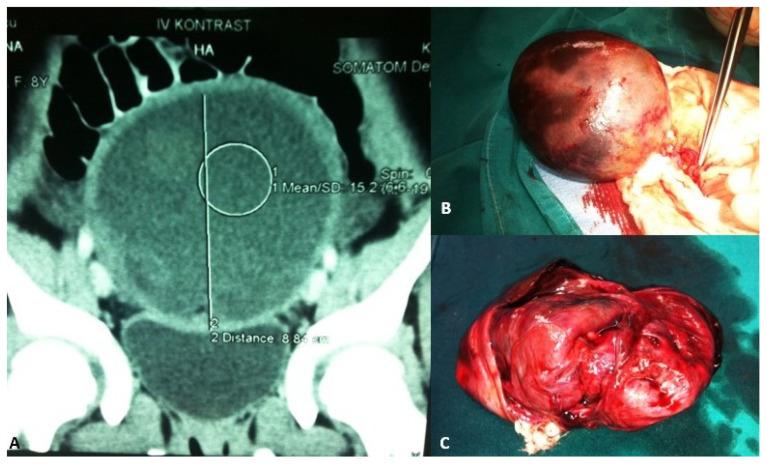

The majority of abdominal masses in female children derive from the ovaries. Ovarian masses in pediatric populations can vary from simple functional cysts to malignant neoplasms. Their incidence, clinical presentation, and histological distribution vary across age groups. In the assessment of ovarian masses in children, the primary aim is to determine the probability of malignancy, as the treatment approaches for benign and malignant lesions are significantly distinct. The primary imaging tool for evaluating ovarian cysts and masses is ultrasound, which can assess the size, location, and characteristics of masses. Magnetic resonance imaging (MRI) or computed tomography (CT) may be used for further evaluation if ultrasound findings are inconclusive or if malignancy is suspected, especially in older adolescents. Serum markers may be considered in older adolescents to help assess the risk of malignancy, though it is less useful in younger populations due to normal developmental variations. Many functional ovarian cysts, especially those detected in fetuses or infants, often resolve spontaneously without intervention. Surgical intervention is indicated in cases of large cysts that cause symptoms, or if there are concerns for malignancy. Common procedures include primarily ovarian sparing laparoscopy or laparotomy. Complications like torsion, rupture, or hemorrhage may require urgent surgical intervention. Treatment should be performed in specialized centers to avoid unnecessary oophorectomies and ensure the best possible outcome for the patient. This comprehensive review aims to provide an overview of the evaluation, diagnosis, and treatment of ovarian masses in the pediatric population. Emphasis is placed on the particularities of the lesions and their management in relation to age subgroups.

女童腹部肿块大多源于卵巢。儿科人群中的卵巢肿块种类繁多,从单纯的功能性囊肿到恶性肿瘤都有。其发病率、临床表现及组织学分布因年龄组而异。在评估儿童卵巢肿块时,主要目的是确定恶性的可能性,因为良性和恶性病变的治疗方法有显著区别。评估卵巢囊肿和肿块的主要影像学工具是超声,它可以评估肿块的大小、位置和特征。如果超声检查结果不明确或怀疑有恶性可能,尤其是年龄较大的青少年,可能会使用磁共振成像(MRI)或计算机断层扫描(CT)进行进一步评估。年龄较大的青少年可考虑检测血清标志物以帮助评估恶性风险,不过由于正常发育变异,血清标志物在年幼儿童中作用较小。许多功能性卵巢囊肿,尤其是在胎儿或婴儿中发现的囊肿,常常无需干预即可自行消退。对于引起症状的大囊肿或怀疑有恶性可能的情况,需进行手术干预。常见手术主要包括保留卵巢的腹腔镜手术或剖腹手术。扭转、破裂或出血等并发症可能需要紧急手术干预。治疗应在专业中心进行,以避免不必要的卵巢切除术,并确保患者获得最佳治疗效果。本综述旨在概述儿科人群卵巢肿块的评估、诊断和治疗。重点在于病变的特殊性及其在不同年龄亚组中的处理。